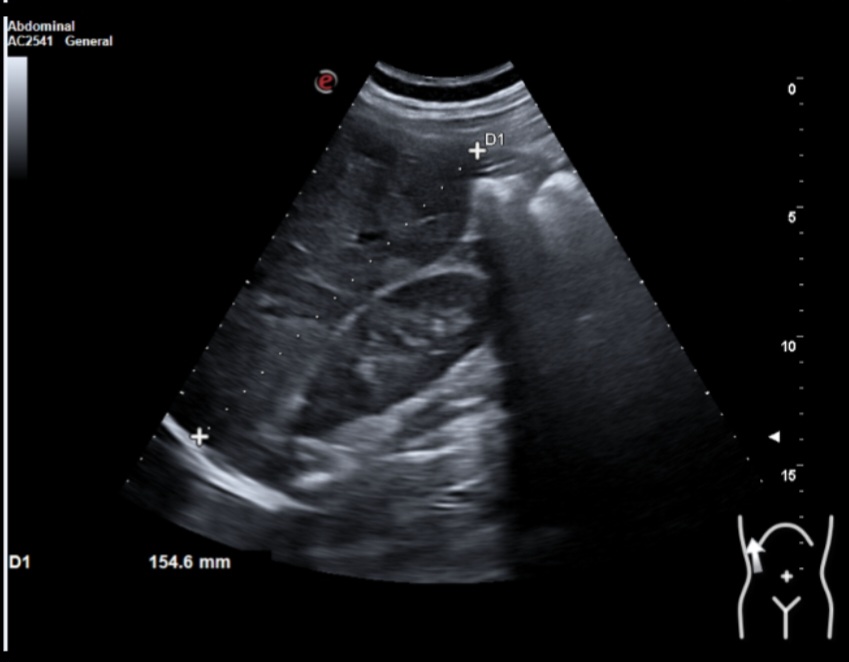

Ecografía clínica: múltiples lesiones en parénquima hepático bien delimitadas de hasta 2 cm, hipoecogénicas, en ambos lóbulos. Tamaño normal del hígado (15 cm) pero bordes obtusos. Vía biliar no dilatada. Vesícula alitiásica. Porta de calibre normal. Área pancreática no visualizada por gas intestinal. Ambos riñones normales. Vejiga vacía, no valorable.

Dados los hallazgos se solicitó ecografía reglada que informaba de múltiples lesiones hepáticas sospechosas y afectación adenopática infradiafragmática. Se recomendó completar estudio mediante TAC estadiaje.

Ante los resultados del TAC sugestivo de neoplasia de colon trasverso con extensa afectación ganglionar locorregional y a distancia a nivel infradiafragmático, afectación ganglionar supradiafragmática y numerosas metástasis hepáticas se solicitó una colonoscopia visualizándose una lesión mucosa de 5 cm de aspecto velloso de la que se tomaron biopsias.